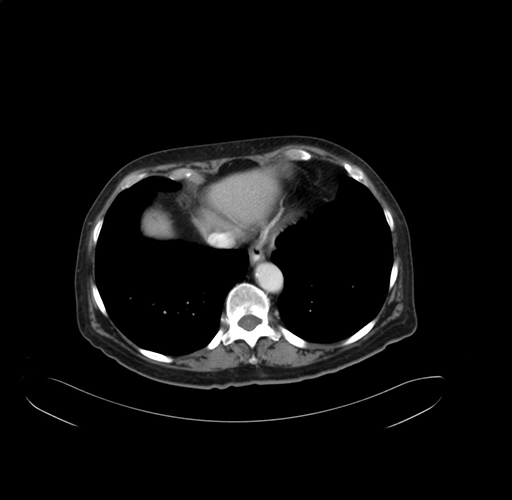

Pre-Chemo: Axial Venous

Axial Venous